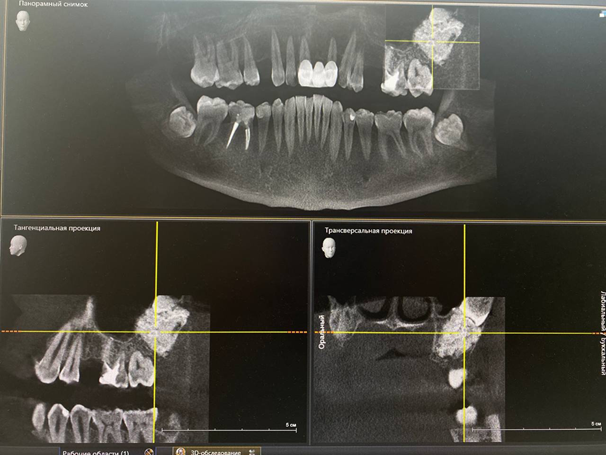

Итак, слева (справа на снимке) мостовидный протез со странной штукой в тканях выше его середины.

История этой женщины в следующем: пациентка пришла к врачу другой клиники и сказала, что хочет имплантацию. Врач сделал ортоснимок — то есть он снял вот этот же кадр, только склеив из нескольких 2D, а не из облака точек в результате множественных измерений КТ. Вот тут и тут больше деталей про то, в чём разница. Коротко — панорамный рентген сшивается из целых плоских снимков геометрическими преобразованиями, а КТ даёт сырые данные, из которых можно построить трёхмерное облако точек и, например, напечатать фрагмент головы пациента со всеми зубами, сосудами и нервами для тренировок перед операцией.

Итак, там вы можете видеть кость, которая поднялась довольно высоко. Врач той клиники решил, что это большая удача, что такой объём кости внезапно сохранился, никакая аугментация не требуется, — и попытался засверлить туда имплантат. Во время операции он понял, что что-то идёт не так и кость слишком твёрдая. Тем не менее он закончил и подождал несколько месяцев. Когда пришло время протезировать (то есть ставить коронку на винт-имплантат), выяснилось, что винт подвижный. То есть имплантат не интегрировался. Его выкрутили, затем поверх поставили мостовидный протез. В середине кости на снимке видно след — «скважину» имплантации.

Когда пациентка пришла к нам по другому вопросу, мы сделали томограмму, увидели результат и подозрительно зашипели. КТ позволяла с высокой степенью достоверности предположить, что это нечто, имеющее все признаки опухоли. Напоминаю, ни один снимок такого типа не даёт ставить диагноз, делать это можно только по гистологии. Но по снимку можно сказать, на какие диагнозы это сильно похоже. С точки зрения принятия решений о лечении дальше это даёт очень много.

Так вот, если вы посмотрите на снимок, то увидите, что костнотканный рисунок наверху и внизу отличается. Плотность и минерализация подозрительного участка этой изменённой костной ткани очень высокая.

По всем признакам это доброкачественная опухоль в теле верхней челюсти. Она характеризуется тем, что плотность кости выше обычной. Причину явления установить пока нельзя, это наука ещё не может однозначно сказать — мы же просто сталкиваемся с последствиями. В общем, что-то в организме пациента привело к тому, что костная ткань стала более плотной: это могла быть генетика, токсикология, инфекция — что угодно, мы не знаем. Образовалась кость с минимальным количеством сосудов, без стандартных механизмов регенерации и тому подобное — нарушился баланс между разными типами клеток в ткани.

Соответственно, стенки шахты имплантата не охватили винт, поскольку за это отвечает именно регенеративный процесс. Скорее всего, костная ткань была плотная настолько, что на срезе кость могла спечься от инструмента врача. В итоге туда, в промежуток между имплантатом и этой новой тканью, пророс эпителий десны, и винт держался на нём.

В общем, пациентка с некоторой долей ужаса отправилась к онкологу (хотя мы сразу предупредили, что, скорее всего, ничего серьёзного). Онколог подтвердил остеому, сказал, чтобы никакой идиот не пытался её разрезать, иссечь или что-то в неё вкрутить, а затем сказал наблюдать. Это одна из самых позитивных вещей, которую только может сказать онколог, кстати.

Пациентка наблюдалась у нас достаточно, чтобы накопить исторические записи. Динамики развития нет, объём сохраняется. Поэтому всё в порядке. Вот снимок через год после обнаружения:

И вот ещё один через два года: